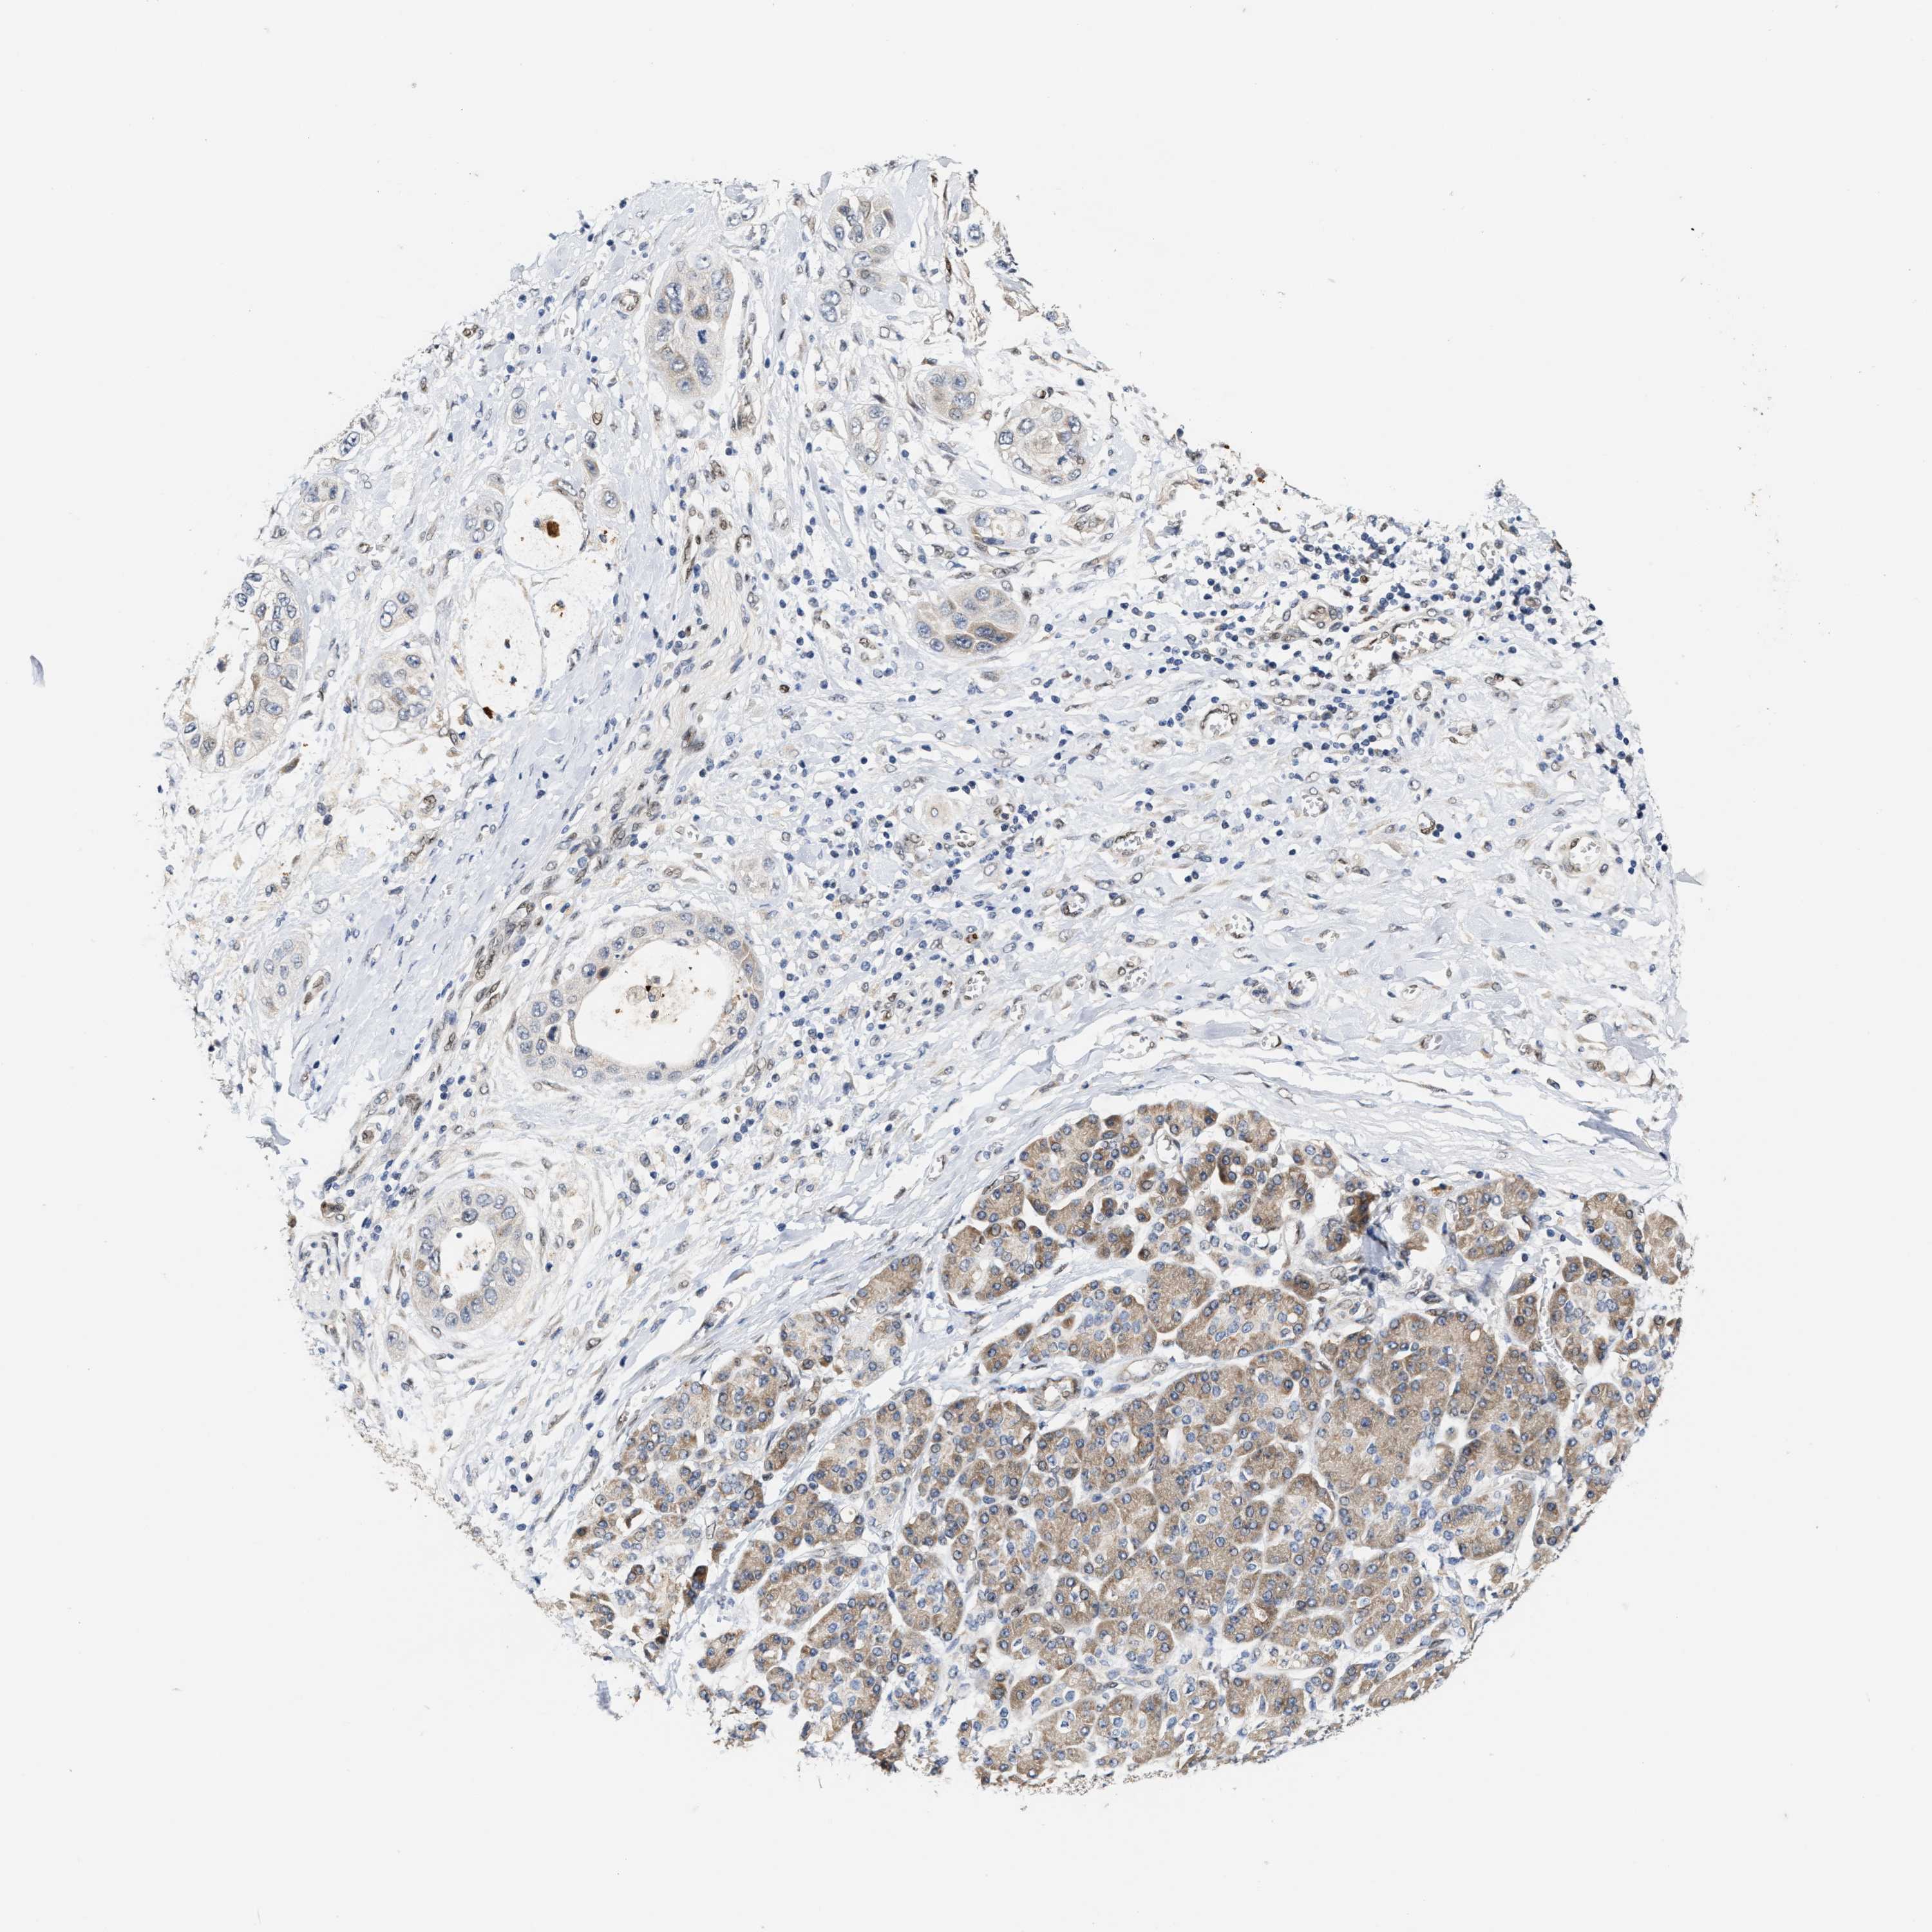

PANCREATIC CANCER - Protein expressioni

A mouse-over function shows sample information and annotation data. Click on an image to view it in a full screen mode. Samples can be filtered based on level of antibody staining by selecting one or several of the following categories: high, medium, low and not detected. The assay and annotation is described here.

Note that samples used for immunohistochemistry by the Human Protein Atlas do not correspond to samples in the TCGA dataset.

Antibody stainingi

Antibody staining in the annotated cell types in the current human tissue is reported as not detected, low, medium, or high, based on conventional immunohistochemistry profiling in selected tissues. This score is based on the combination of the staining intensity and fraction of stained cells.

Each image is clickable and will lead to virtual microscopy that enables deeper exploration of all samples and also displays staining intensity scores, fraction scores and subcellular localization as well as patient and tissue information for each sample.

Antibody HPA025958

Antibody CAB020722

Staining

High

Medium

Low

Not detected

Intensity

Strong

Moderate

Weak

Negative

Quantity

>75%

75%-25%

<25%

None

Location

Nuclear

Cytoplasmic/membranous

Cytoplasmic/membranous,nuclear

Adenocarcinoma, NOS

Adenocarcinoma, metastatic, NOS